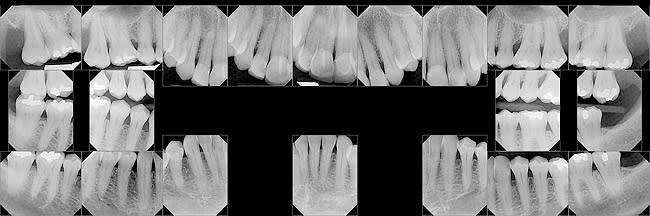

A current set of complete radiographs should be available before beginning the clinical examination. The radiographic series should consist of five maxillary anterior films, three mandibular anterior films, and two posterior films in each quadrant. Two vertical bitewing films on each side complete the series. The advantage of vertical bitewings is that they allow the interproximal osseous margins to be visualized with minimal distortion, which helps identify areas of osseous loss.

The radiographs are evaluated to identify carious lesions, the presence of endodontic lesions or inadequate previous endodontic treatment, areas of osseous loss, furcation involvement, impacted teeth, inadequate or failing restorations, and areas of pathologic osseous lesions. Panoramic films can serve as an adjunct to the series of intraoral films to screen for pathology. They are not adequate to use as the only source of radiographic evidence to determine the presence of periodontal osseous loss and to identify areas requiring restorative treatment. The final piece of information to be gleaned from the radiographic examination is an initial analysis of implant needs. Missing teeth that need to be replaced or those with poor prognoses should be noted.

Figure 1 is a representative complete set of radiographs illustrating severe osseous loss affecting Nos. 2 and 15, significant angular osseous defects mesial to Nos. 3 and 14, a horizontal osseous defect between Nos. 11 and 12 (note the change of coronal osseous height between the Nos. 11 and 12 interproximal space and the normal Nos. 12 and 13 area), and a subtle osseous change in the interproximal space Nos. 21 and 22. The change was related to the presence of a gingival cyst, which was biopsied. The probing record in Figure 2 is of the same patient represented in the radiographs.